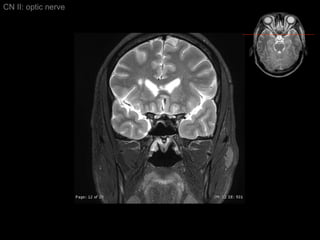

CN II: optic nerve Axial T2/ inferior to superior

CN II: optic nerve